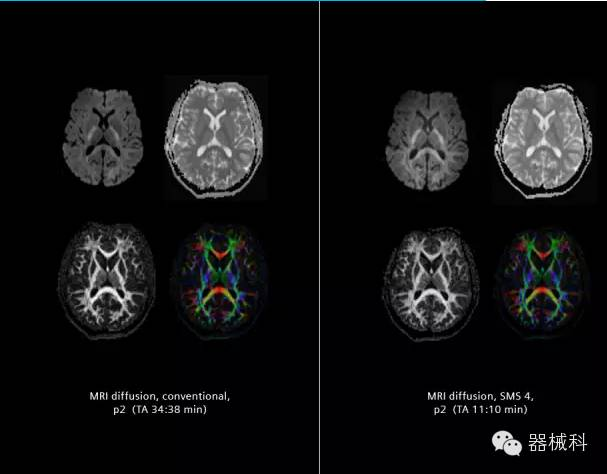

SMS技術(shù)可以將原本用于科研的高級成像技術(shù)轉(zhuǎn)化成臨床常規(guī)。

SMS可以有效提升高級功能成像精準(zhǔn)度。

擁有了SMS“同時多層”采集技術(shù)之后,用戶可以在非常短的時間內(nèi)完成MR掃描,結(jié)合西門子靜音技術(shù),大大提高患者的舒適性,或在單位時間內(nèi)采集更多的數(shù)據(jù),也可以得到高精度、高準(zhǔn)確性、大數(shù)量的功能成像數(shù)據(jù),為臨床和科研提供強(qiáng)大的支持。專家認(rèn)為,SMS“同時多層”采集技術(shù)未來在 提高成像質(zhì)量、外科手術(shù)計劃、降低術(shù)后神經(jīng)功能缺陷、提高fMRI的時間采集效率、提高靜息態(tài)功能磁共振數(shù)據(jù)質(zhì)量等方面將帶來深遠(yuǎn)影響,希望該技術(shù)可以盡早面世,引領(lǐng)磁共振進(jìn)入多層時代!